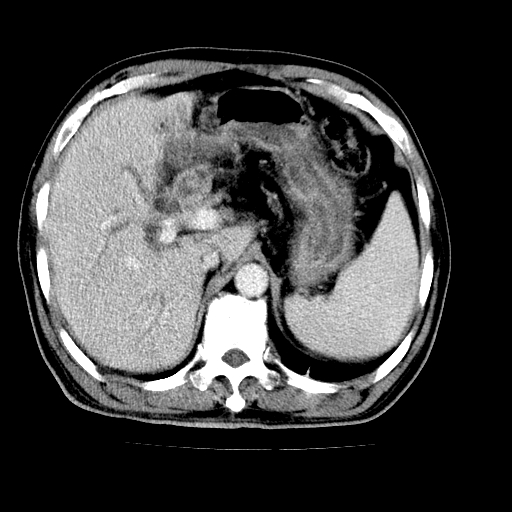

男,66岁,上腹部不适、黄染一周。彩超示:肝左叶占位,肝内胆管扩张,胆总管扩张,胆总管占位?

肝左叶不规则软组织肿块影,边缘不规整邻近肝实质受累分界不清;肝内胆管(左叶)明显扩张成“软藤状”,诊断:肝左叶胆管细胞癌。

肝左叶占位性病变,并胆管扩张,符合胆管细胞癌ct表现,门脉左支受累,左肾囊肿。窗宽太窄了,其他的看不清

左叶胆管细胞癌累及胆总管,门脉左支受侵,慢性胆囊炎胆结石,左肾小囊肿